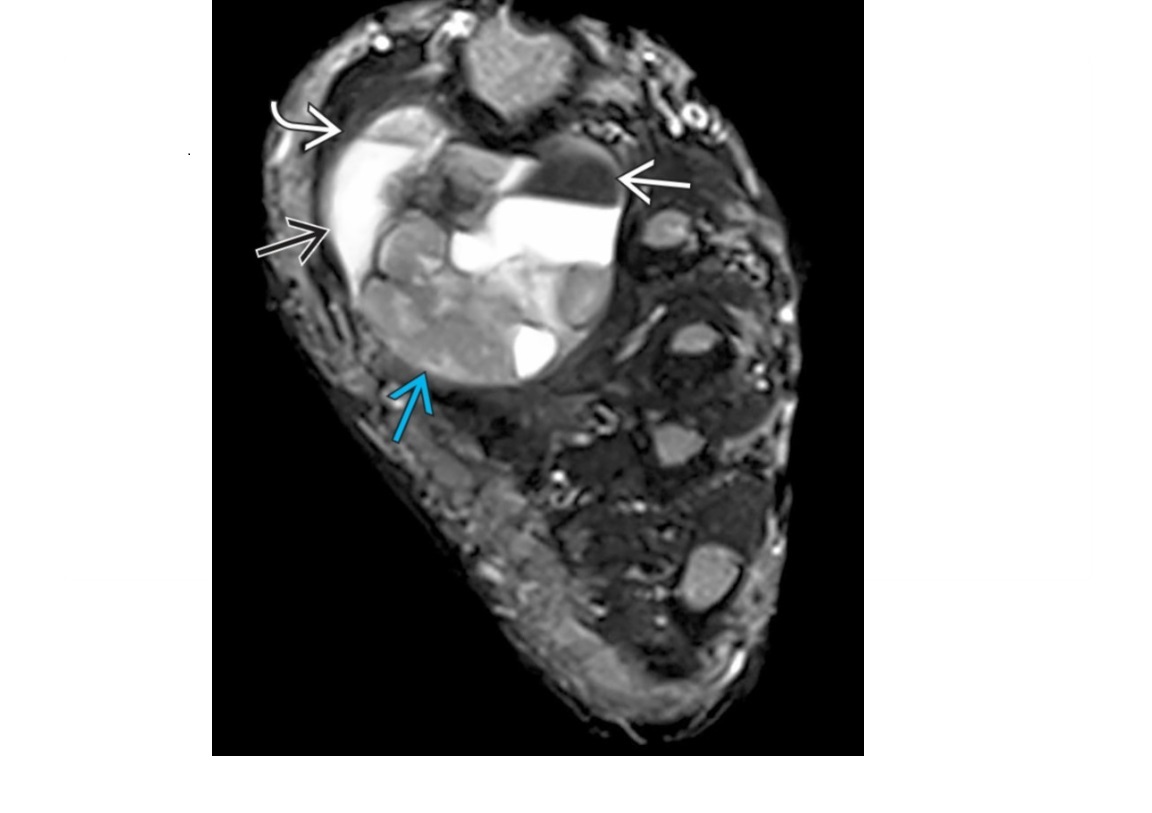

synovial sarcoma

Triple sign

Heterogeneous signal (combination of low, intermediate, and high) T2 signal from:

Solid mass

haemorrhage + necrosis

calcification (1/3).

Bowl of grapes sign = multiloculated appearance of mass with internal septa

Heterogenous enhancement of the solid components.

little to no perilesional oedema

Classic history -

paediatric patient with a multi-cystic appearing mass with well-defined margins around the knee joint

NOT in joint ie DOESNT arise from the synovium. Close to joint